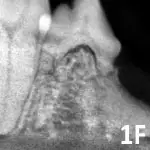

Stage 4: Extensive hard tissue loss. Most of the tooth loses integrity. In stage 4A (See Figure 1D), the crown and root are equally affected; in stage 4B (See Figure 1E), the crown is more severely affected than the root; in stage 4C (See Figure 1F), the root is more severely affected than the crown.

Figure 1F

Mandibular fourth premolar affected by stage 4C tooth resorption.